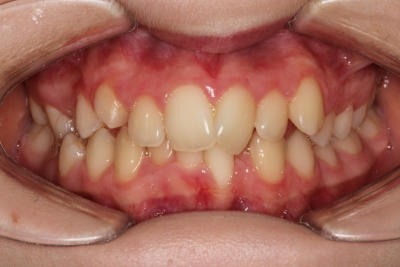

Crowding – Child case